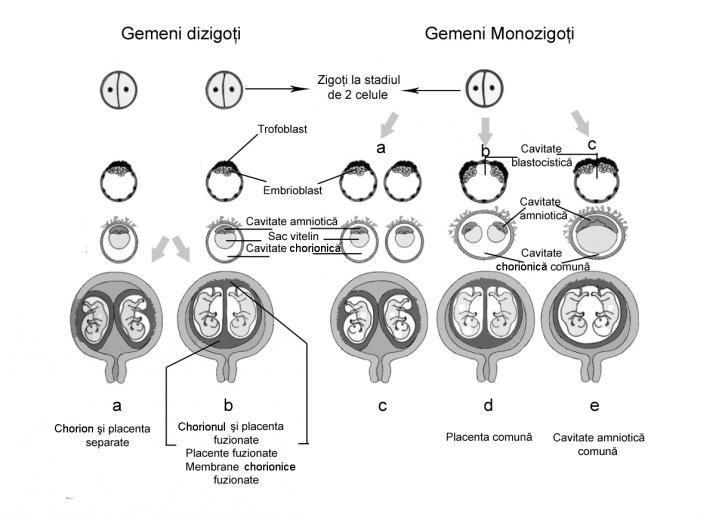

SARCINA MULTIPLA

Sarcina Multipla Definitie: dezvoltarea simultana a doi sau mai multi feti in cavitatea uterina (gemelari, tripleti, etc.). Sarcina gemelara are o frecventa de 1 la 85 de nasteri.[4] Poate fi: - &nCiteste tot ... 1290 cuvinte

Dimensiune mica

+ cu imagini |

Formularea diagnosticului ecografic obstetrical

Formularea diagnosticului ecografic obstetrical Diagnosticul ecografic obstetrical va cuprinde sarcina monofetala sau multipla (cu precizarea amnionicitatii si chorionicitatii), viabilitatea fetala (fat viu, etc., cu precizarea prezenCiteste tot ... 94 cuvinte